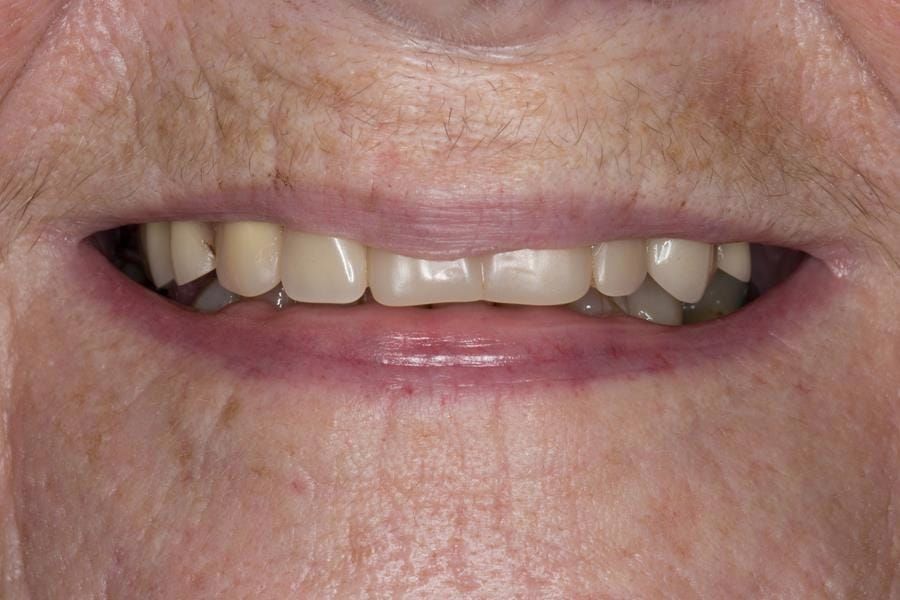

Following consultation and second discussion appointment the patient chose to have option 2 namely, a window denture - maxillary cobalt chromium based partial denture. The clinical situation and treatment process is shown in detail below with photographs. The patient was successfully rehabilitated with this and her quality of life considerably improved. The clinical work was provided by Finlay and the technical work by Rowan.